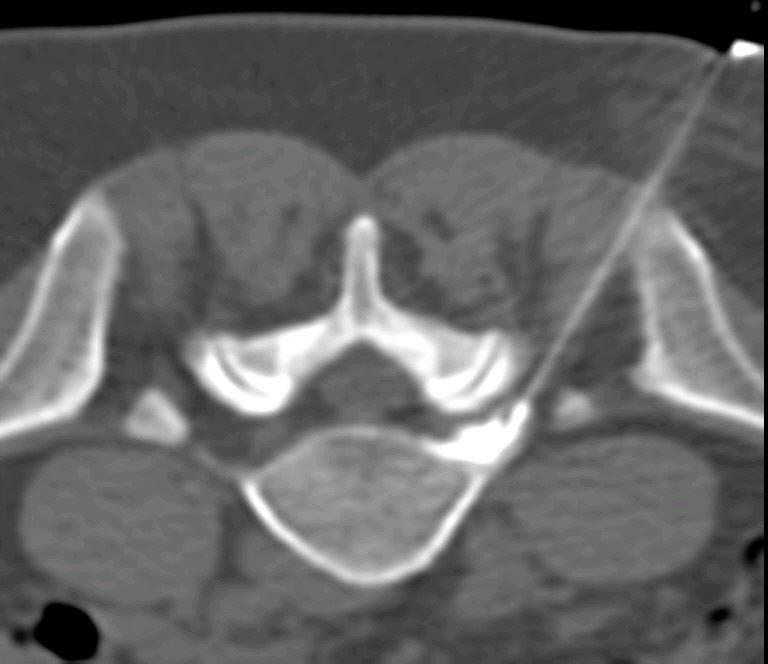

Zu den gängigen Verfahren gehören z.B. Eingriffe an der Wirbelsäule zur Schmerzlinderung an den Wirbelbogengelenken (Facettengelenkdenervation), Behandlung von entzündlichen Reizzuständen der Nervenwurzeln (periradikuläre Therapie PRT) oder zur Stabilisierung bruchgefährdeter Wirbel (Vertebroplastie). Wir führen diese Eingriffe zumeist im Rahmen interdisziplinärer Behandlungskonzepte durch, die meist eine orthopädische und krankengymnastische Therapie einschließen.